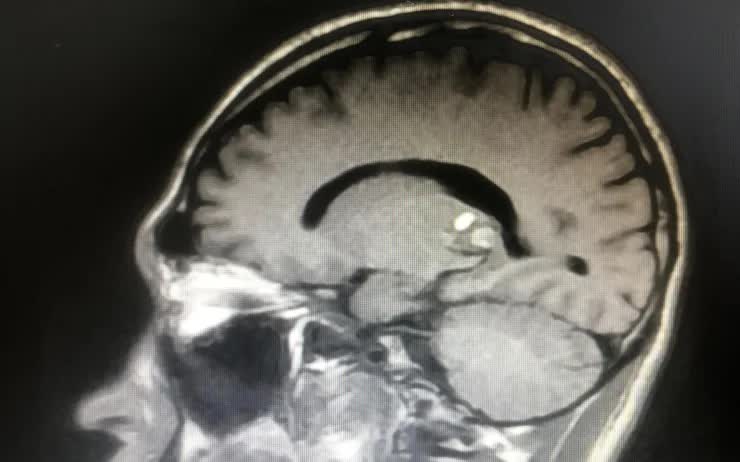

Hãy tưởng tượng một cậu bé 11 tuổi, đang ở độ tuổi hiếu động và khám phá thế giới, đột nhiên bắt đầu gặp khó khăn với thị lực. Ban đầu chỉ là nhìn mờ, rồi dần dần, tay phải viết lóng ngóng, chân phải bước đi không vững. Tình trạng xấu đi nhanh chóng khiến gia đình lo lắng đưa bé đến bệnh viện. Sau các xét nghiệm kỹ lưỡng, các bác sĩ phát hiện ra thủ phạm là một khối u đang chảy máu (gọi là cavernoma) nằm ở tiểu não – phần não chịu trách nhiệm kiểm soát sự cân bằng và phối hợp động tác. Đây không phải là một căn bệnh thông thường, mà là một thử thách đòi hỏi sự can thiệp nhanh chóng và chính xác.

Khối u ở não. Ảnh minh họa